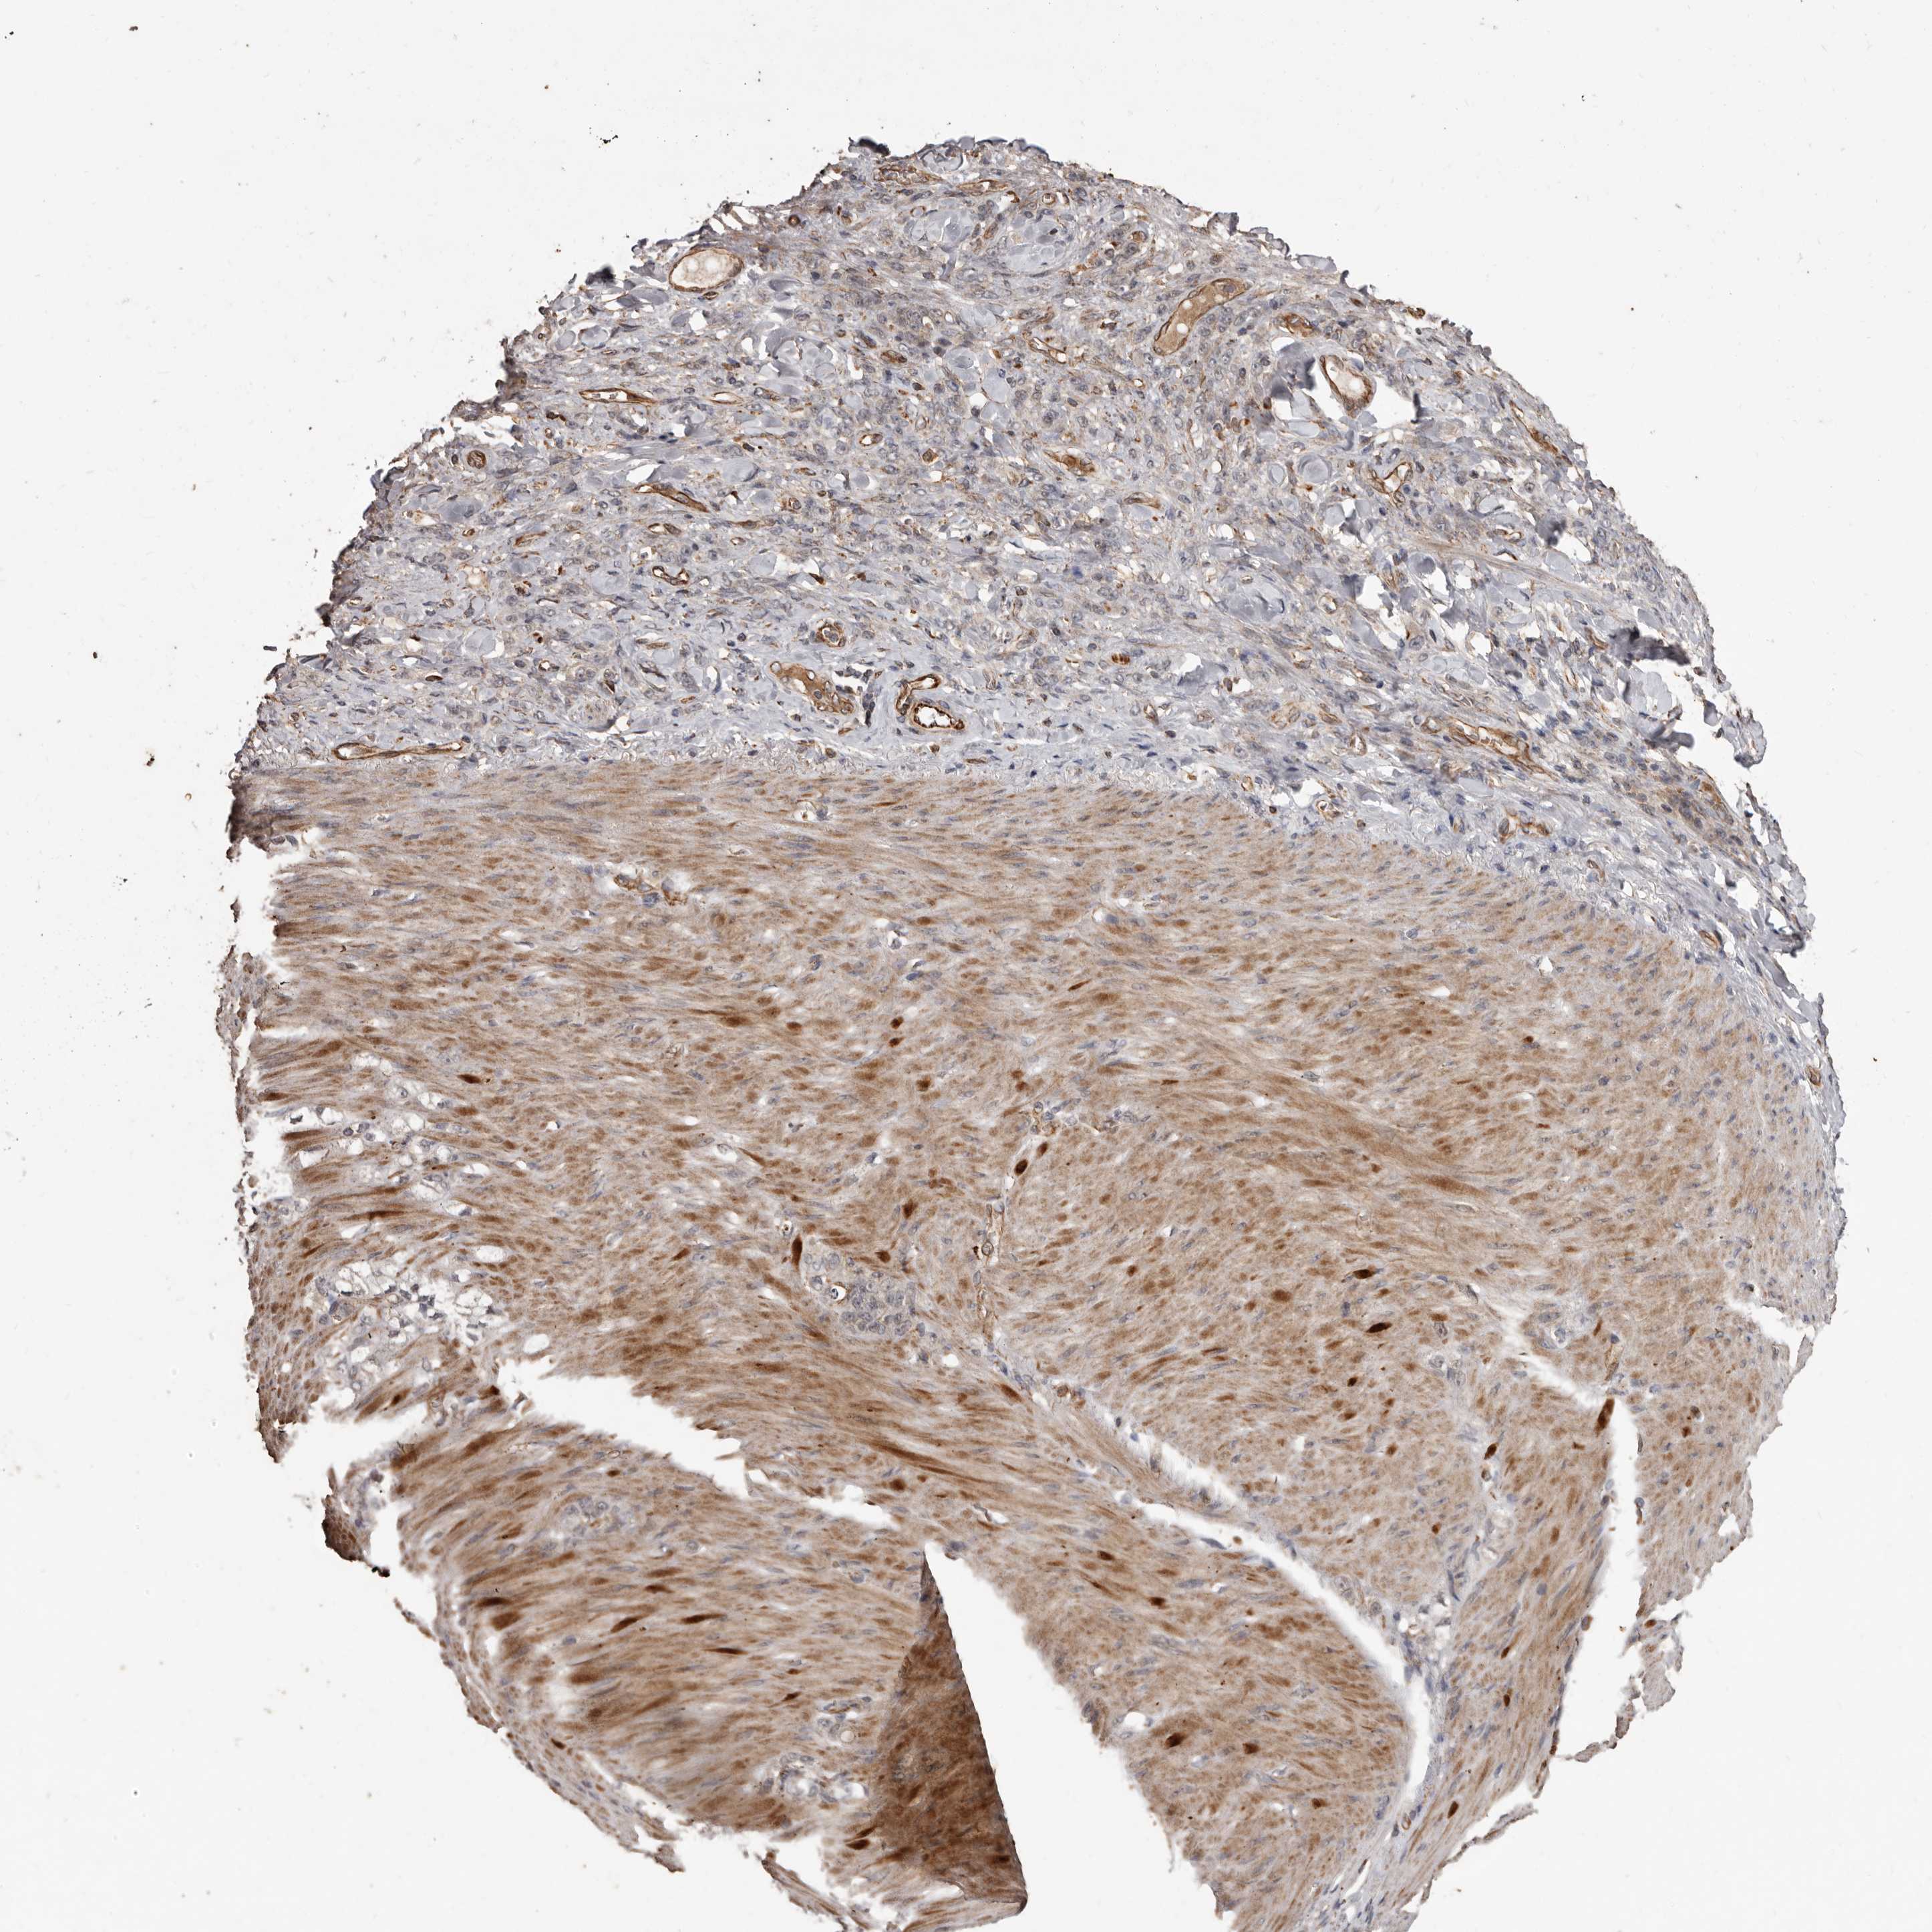

STOMACH CANCER - Protein expressioni

A mouse-over function shows sample information and annotation data. Click on an image to view it in a full screen mode. Samples can be filtered based on level of antibody staining by selecting one or several of the following categories: high, medium, low and not detected. The assay and annotation is described here.

Antibody stainingi

Antibody staining in the annotated cell types in the current human tissue is reported as not detected, low, medium, or high, based on conventional immunohistochemistry profiling in selected tissues. This score is based on the combination of the staining intensity and fraction of stained cells.

Each image is clickable and will lead to virtual microscopy that enables deeper exploration of all samples and also displays staining intensity scores, fraction scores and subcellular localization as well as patient and tissue information for each sample.

Antibody HPA029455

Staining

High

Medium

Low

Not detected

Intensity

Strong

Moderate

Weak

Negative

Quantity

>75%

75%-25%

<25%

None

Location

Nuclear

Cytoplasmic/membranous

Cytoplasmic/membranous,nuclear

Adenocarcinoma, NOS